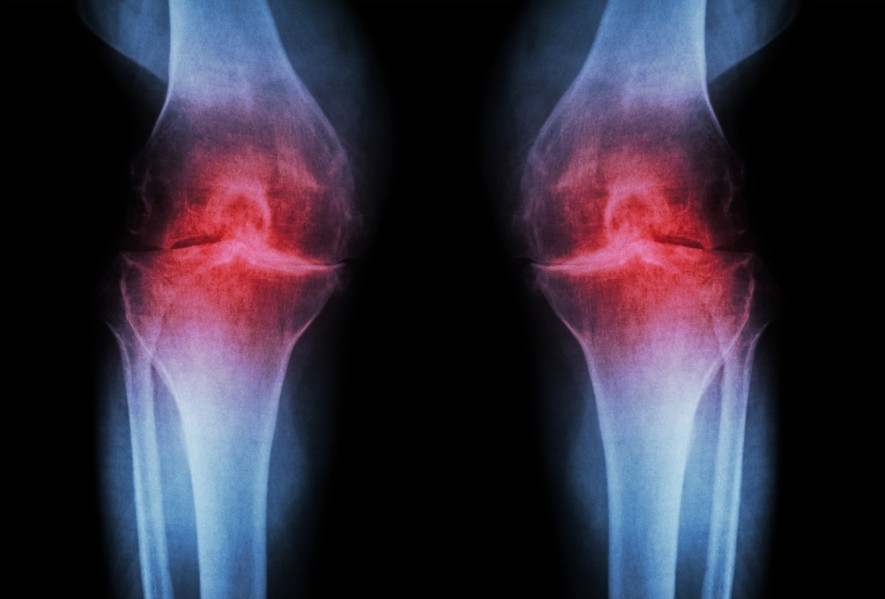

Notera de områden där brosket har brutits ner, vilket är karakteristiskt för knäartros.

Knäartros, också känd som gonartros, är en diagnos som huvudsakligen orsakas av åldersrelaterad slitage på knäleden. Knäledsartros är den mest förekommande formen av artros, en sjukdom där brosket som skyddar och ger glidning i leden bryts ner över tid.

Brosk fungerar normalt som stötdämpare mellan benen i en led, och när det bryts ner kan det orsaka smärta, stelhet och svullnad. På längre sikt kan det till slut orsaka försämrad och smärtsam rörlighet i leden, vilket är vanligt hos personer med knäartros.